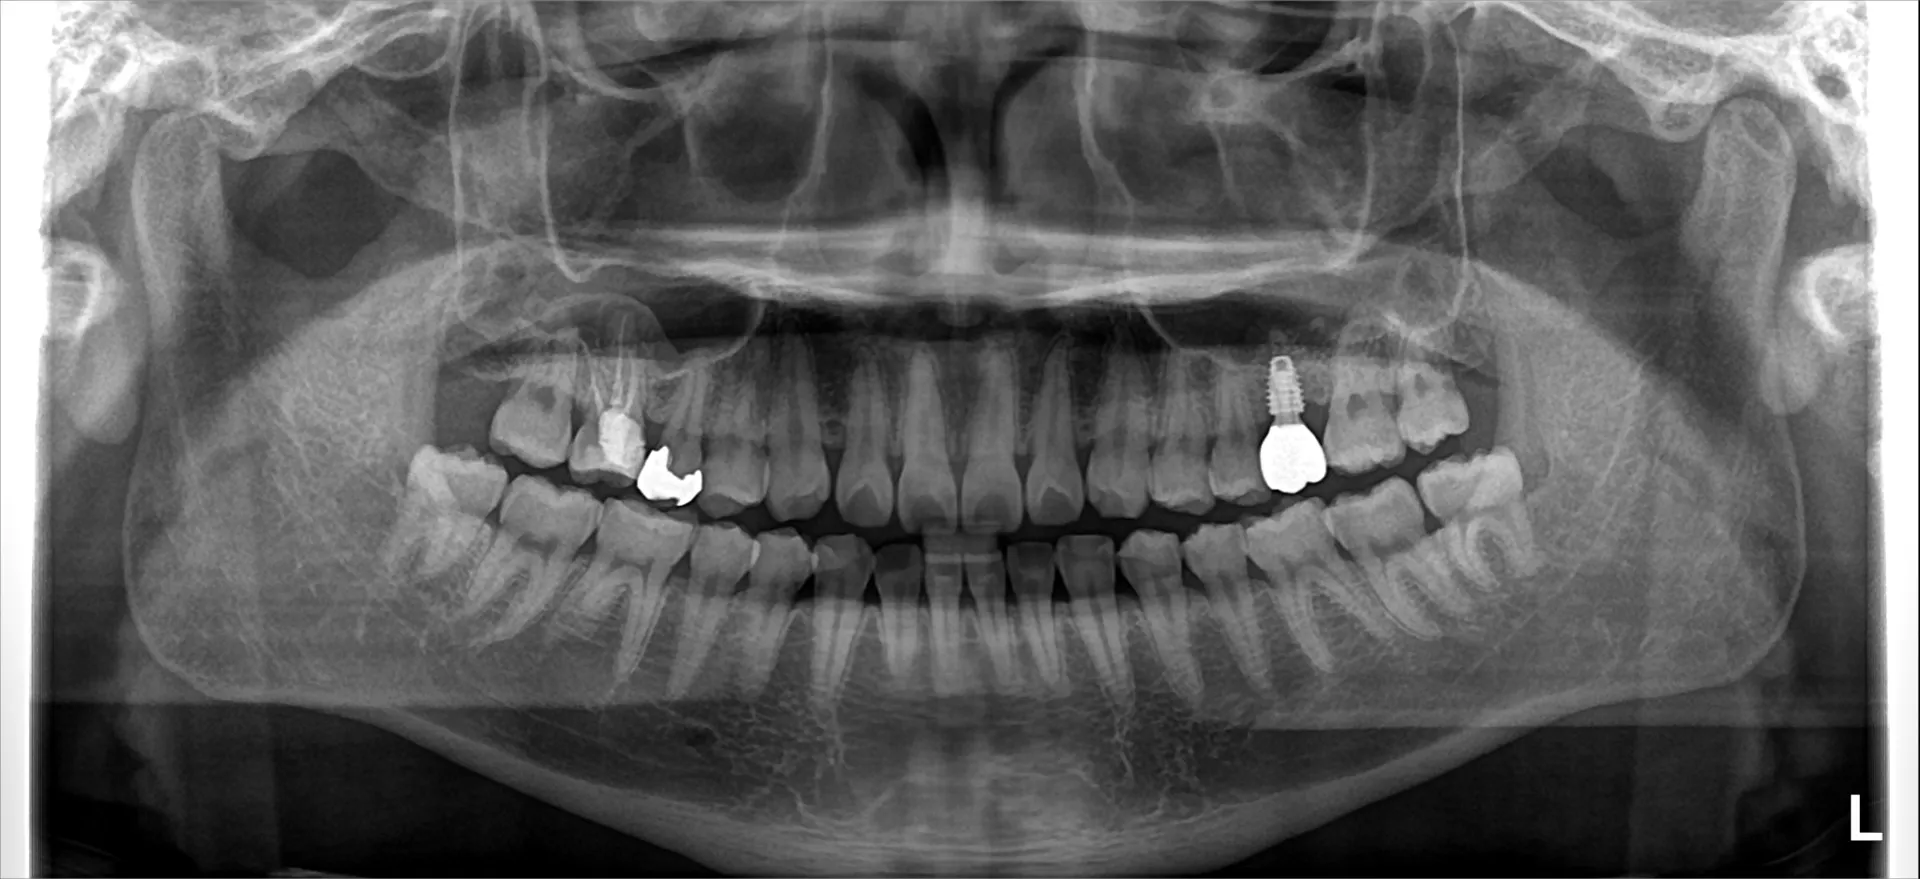

歯のインプラント治療は顎の骨にインプラント体(フィクスチャー)と呼ばれるネジを入れ込み、そこから人工の歯を立ち上げる方法です。

歯を抜歯した方など歯が無い所に行う方法で、いわゆる差し歯と似た構造ですが、歯の根っこが残っているのが差し歯で、根っこ自体から作り上げるのがインプラントです。

歯を抜いた状態を放置していると歯を支えていた骨はどんどんと無くなっていきます。